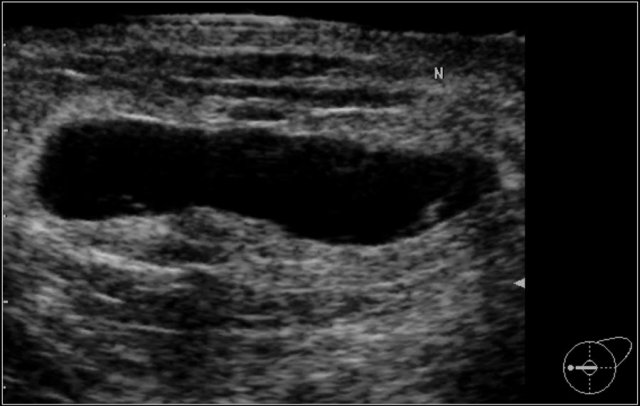

This patient presented with a mass on the mammogram at screening, which was assigned as BI-RADS 0 (needs additional imaging evaluation).

Additional ultrasound demonstrated that the mass was caused by an intramammary lymph node.

The final assessment is BI-RADS 2 (benign finding).

Don't forget to mention in the report that the lymph node on US corresponds with the noncalcified mass on mammography.

In the paragraph on location we will discuss how we can be sure that the lymph node that we found with ultrasound is indeed the same as the mammographic mass.